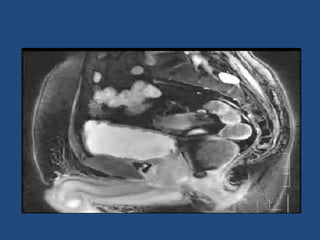

Prostate cancer is the second most common cancer globally, with varying incidence rates influenced by geography and lifestyle changes. In India, prostate cancer cases are rising due to urban migration and increased medical awareness, with current rates approaching those in Western countries. Treatment options vary by stage, including watchful waiting, surgery, radiation therapy, and hormonal treatment, each tailored to patient-specific factors.